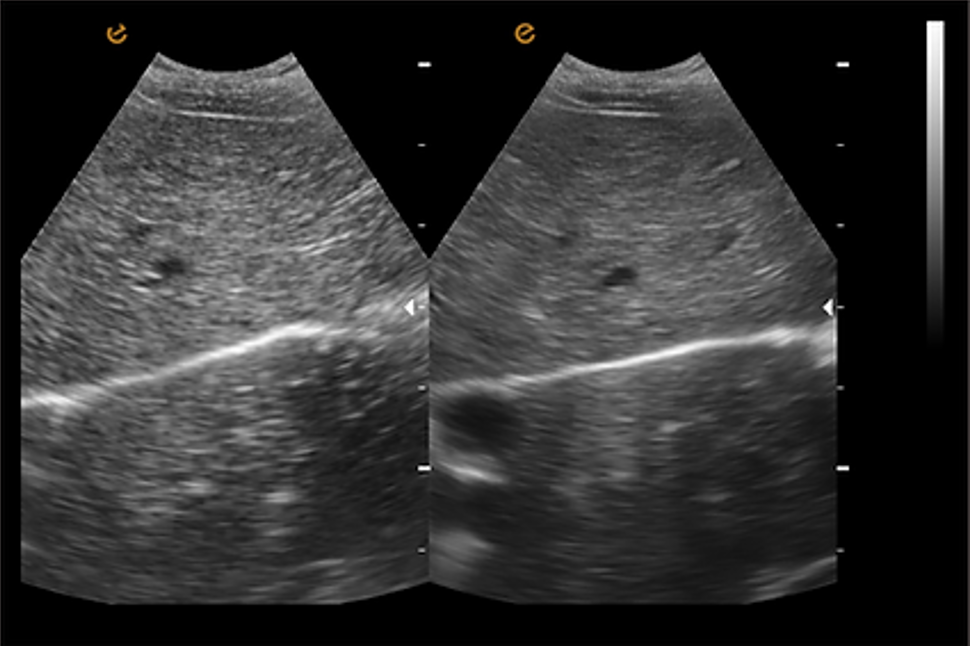

เทคโนโลยีลดจุดรบกวน ePure เทคโนโลยีลดจุดรบกวน (Speckle Reduction Technology) เป็นเทคโนโลยีที่ช่วยลดเสียงรบกวนที่เกิดจากคลื่นสะท้อน (echoes) ได้อย่างมีประสิทธิภาพ และปรับความสม่ำเสมอของชั้นเนื้อเยื่อต่างๆ ให้เหมาะสม เพื่อให้ได้ภาพคุณภาพสูงสุดที่มีความคมชัดและขอบภาพที่ชัดเจน |